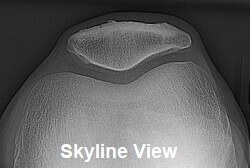

Standard x-rays don’t usually show up the problem, although a “skyline view x-ray” taken from the side of the leg can be used to see the back of the kneecap.